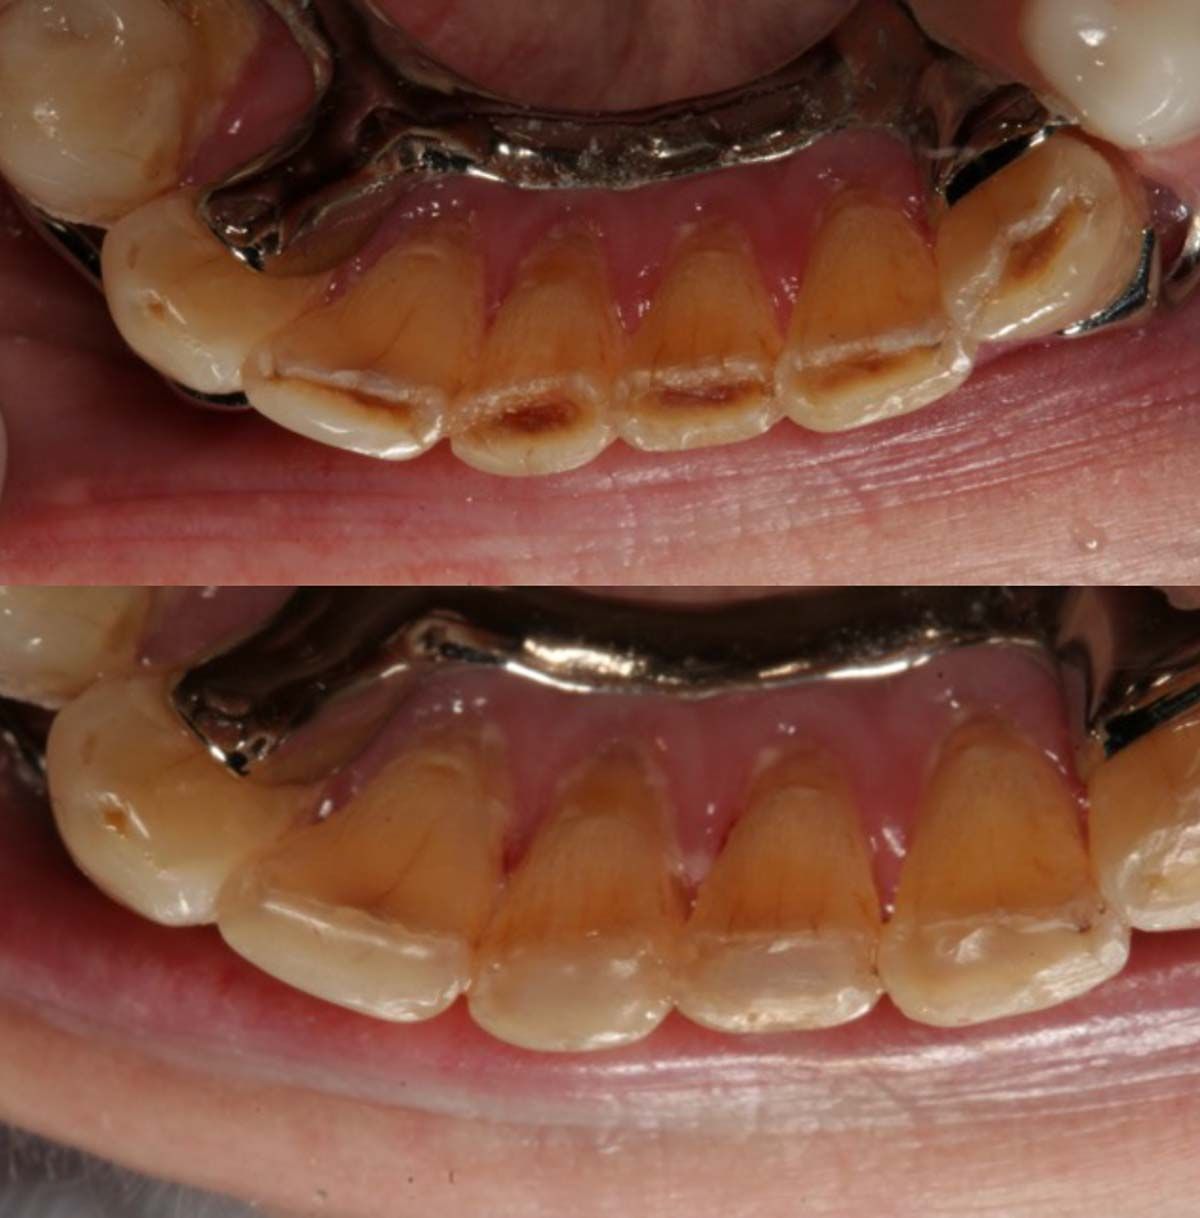

We used to try showing patients their clinical situation on 2D x-rays and demonstrating treatment using models. Later, digital intraoral cameras helped, but they could not show much more than what a patient could see in a mirror. Today, it is possible to show patients every angle of their clinical situation in hyperrealistic 3D with a CBCT scan. Now, when I recommend treatment to patients and they ask why, I am armed with an interactive image captured by my CS 8200 3D extraoral imaging system (Carestream Dental). I scroll through the tooth and bone, point out lesions below the surface, and show why there is or is not enough bone for an implant. If you use something like the Prosthetic-Driven Implant Planning module to automatically merge an intraoral scanner file with the CBCT scan, you create an even more accurate picture. How much easier is it for the patient to accept treatment when they are seeing the end results of that treatment?

Suppose CBCT has revealed that the issue your patient is experiencing requires a specialist. A 3D scan tells me when it is best to refer treatment, but that can be frustrating and confusing to a patient who was not expecting a second appointment at another office. In that case, the 3D scan lets me prepare patients for the next steps. Yes, they are being sent to a specialist, but they will have realistic expectations about what the next doctor might find and recommend for treatment. Because I also send the scan to the specialist, there are no surprises for anybody; patients do not feel like they are arriving at another office only to be blindsided.